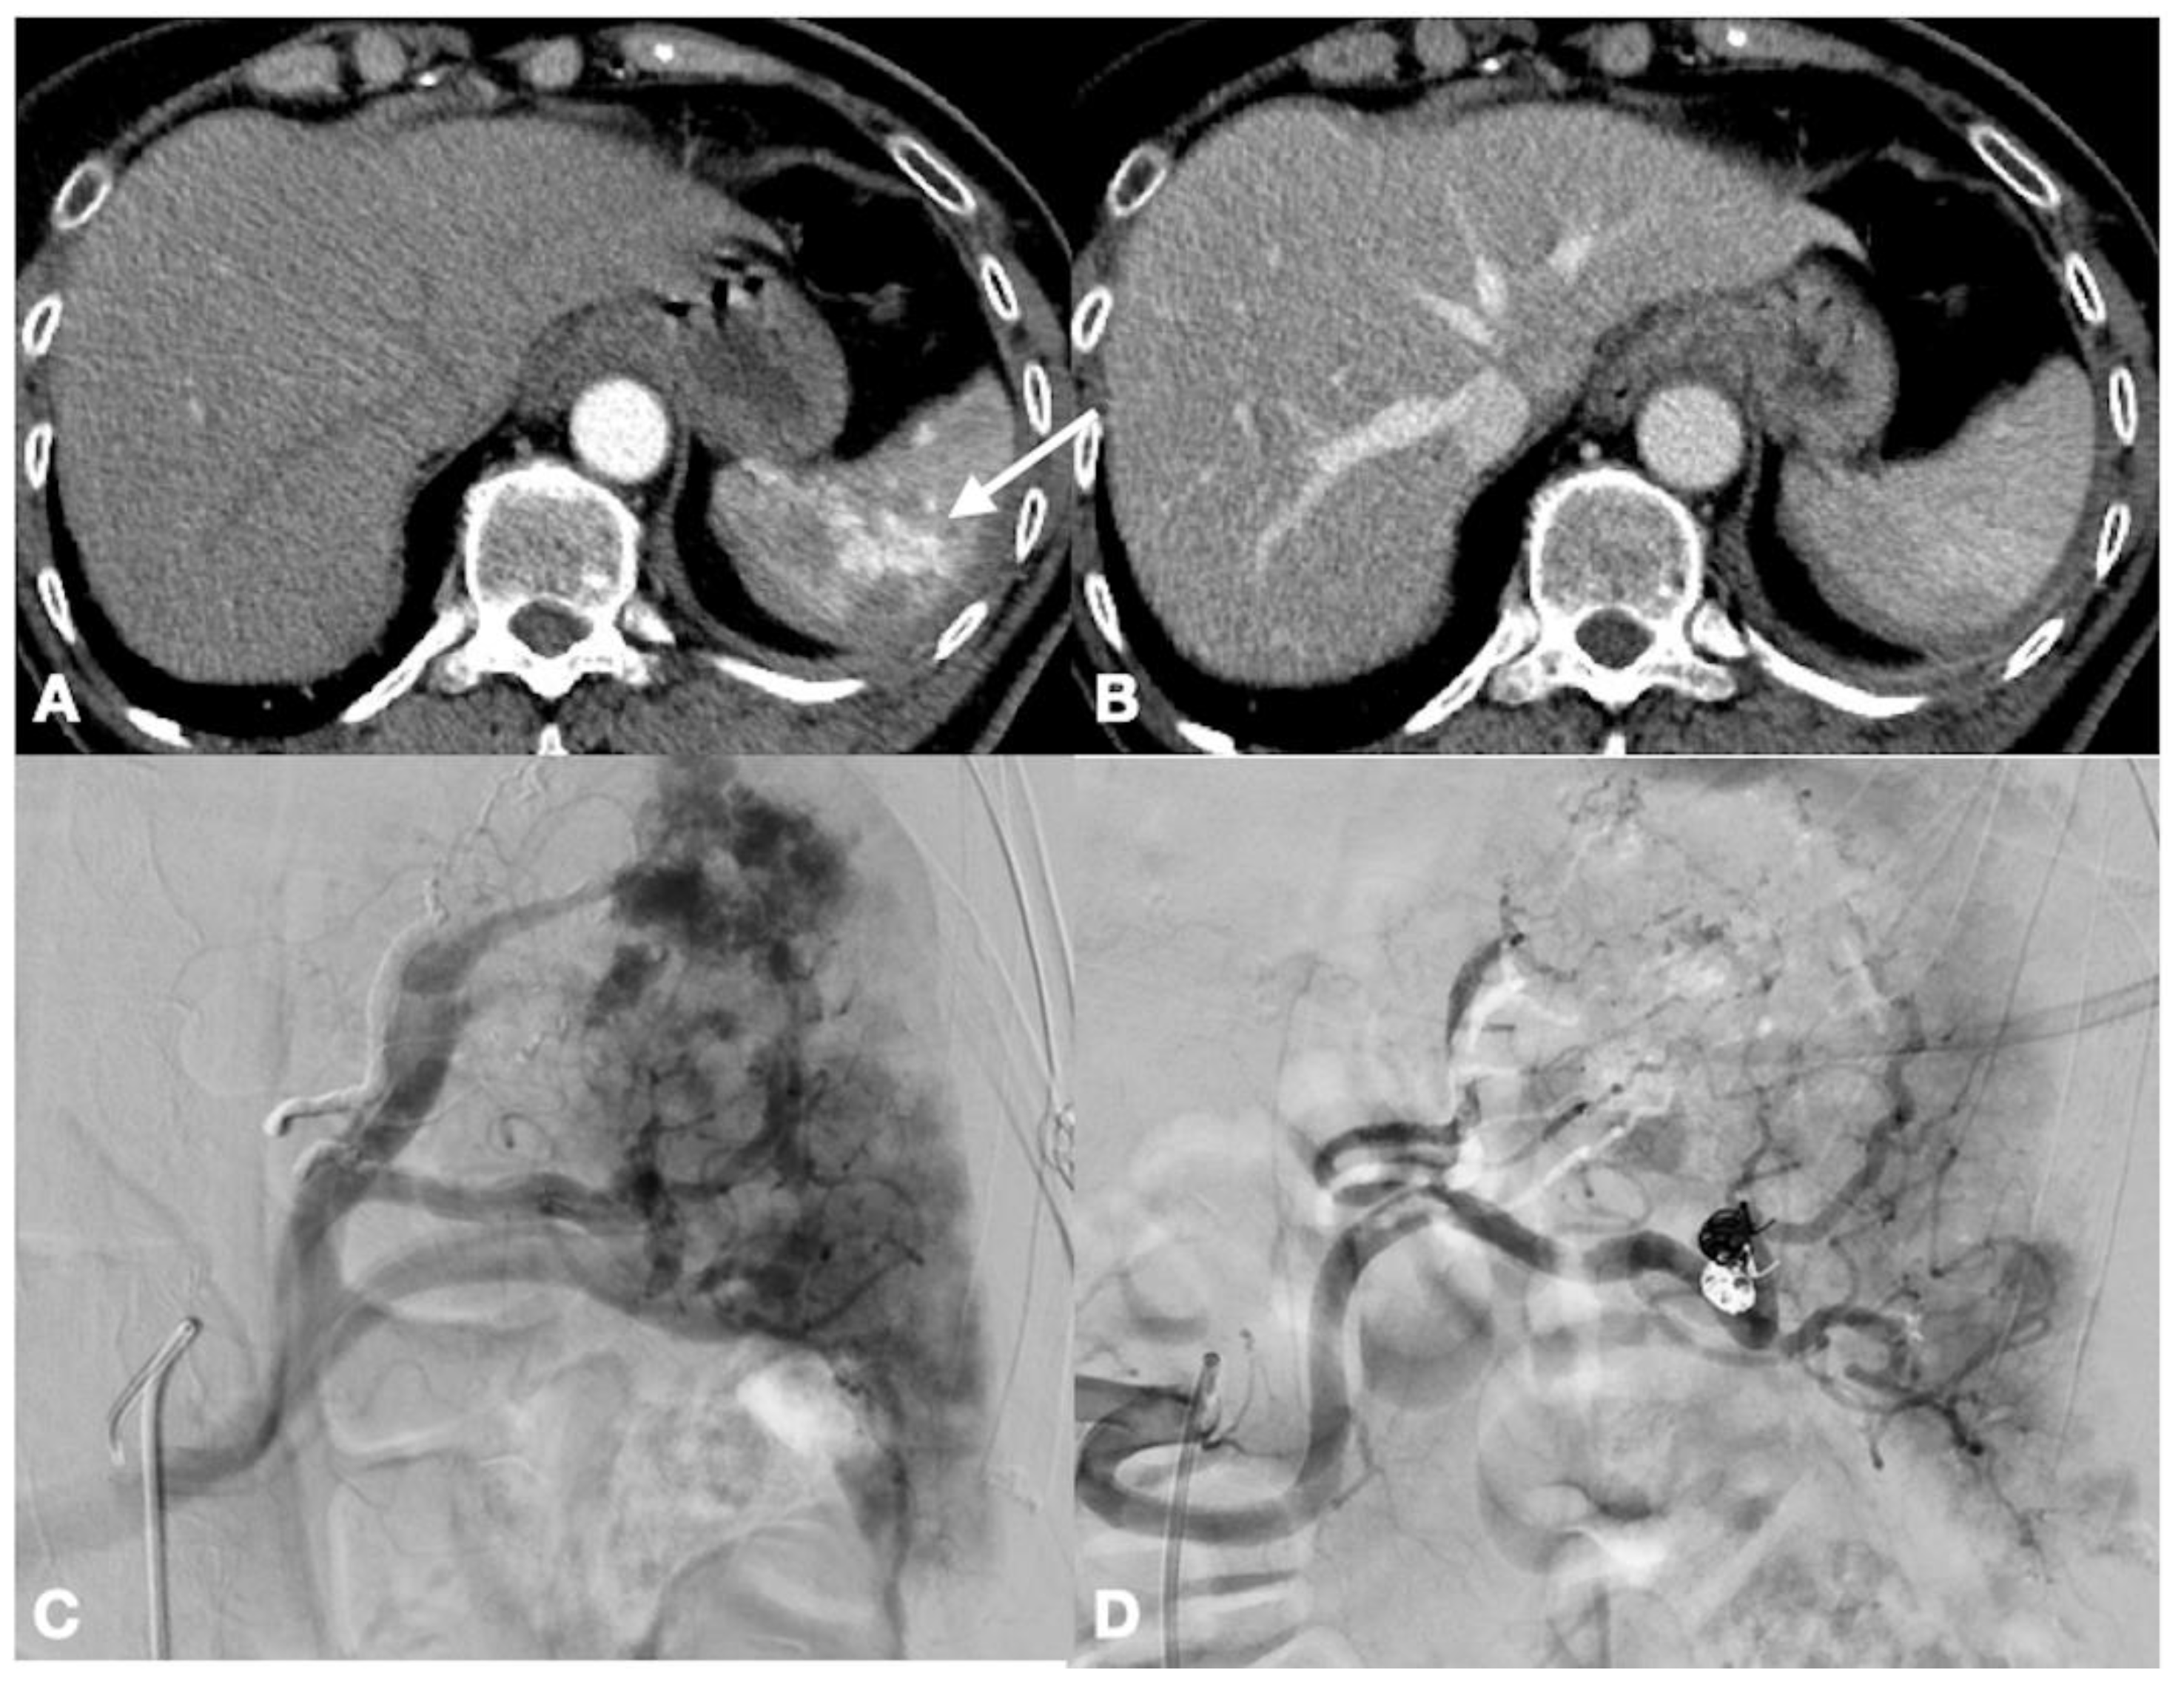

- Iacobellis, F.; Scaglione, M.; Brillantino, A.; Scuderi, M.G.; Giurazza, F.; Grassi, R.; Noschese, G.; Niola, R.; Al Zuhir, N.Y.S.; Romano, L. The additional value of the arterial phase in the CT assessment of liver vascular injuries after high-energy blunt trauma. Emerg. Radiol. 2019, 26, 647–654. [Google Scholar] [CrossRef]

- Iacobellis, F.; Ierardi, A.M.; Mazzei, M.A.; Biasina, A.M.; Carrafiello, G.; Nicola, R.; Scaglione, M. Dual-phase CT for the assessment of acute vascular injuries in high-energy blunt trauma: The imaging findings and management implications. Br. J. Radiol. 2016, 89, 20150952. [Google Scholar] [CrossRef]

- Brillantino, A.; Iacobellis, F.; Festa, P.; Mottola, A.; Acampora, C.; Corvino, F.; Del Giudice, S.; Lanza, M.; Armellino, M.; Niola, R.; et al. Non-Operative Management of Blunt Liver Trauma: Safety, Efficacy and Complica-tions of a Standardized Treatment Protocol. Bull. Emerg. Trauma 2019, 7, 49–54. [Google Scholar] [CrossRef] [PubMed]

- Coccolini, F.; Panel, T.W.E.; Coimbra, R.; Ordonez, C.; Kluger, Y.; Vega, F.; Moore, E.E.; Biffl, W.; Peitzman, A.; Horer, T.; et al. Liver trauma: WSES 2020 guidelines. World J. Emerg. Surg. 2020, 15, 24. [Google Scholar] [CrossRef]